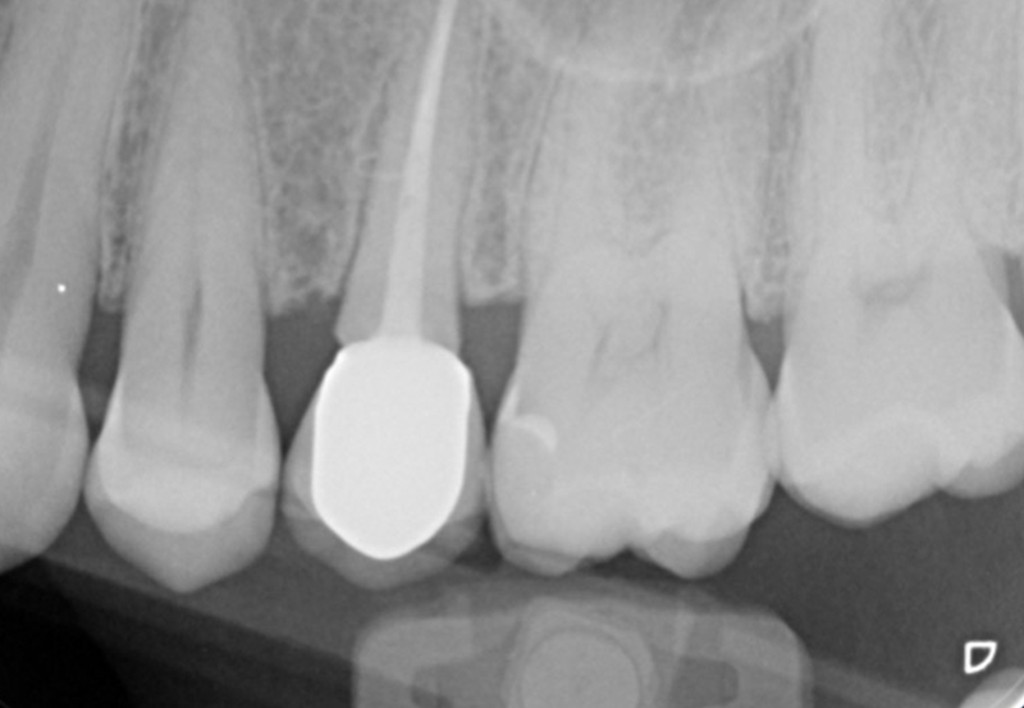

Galleria fotografica